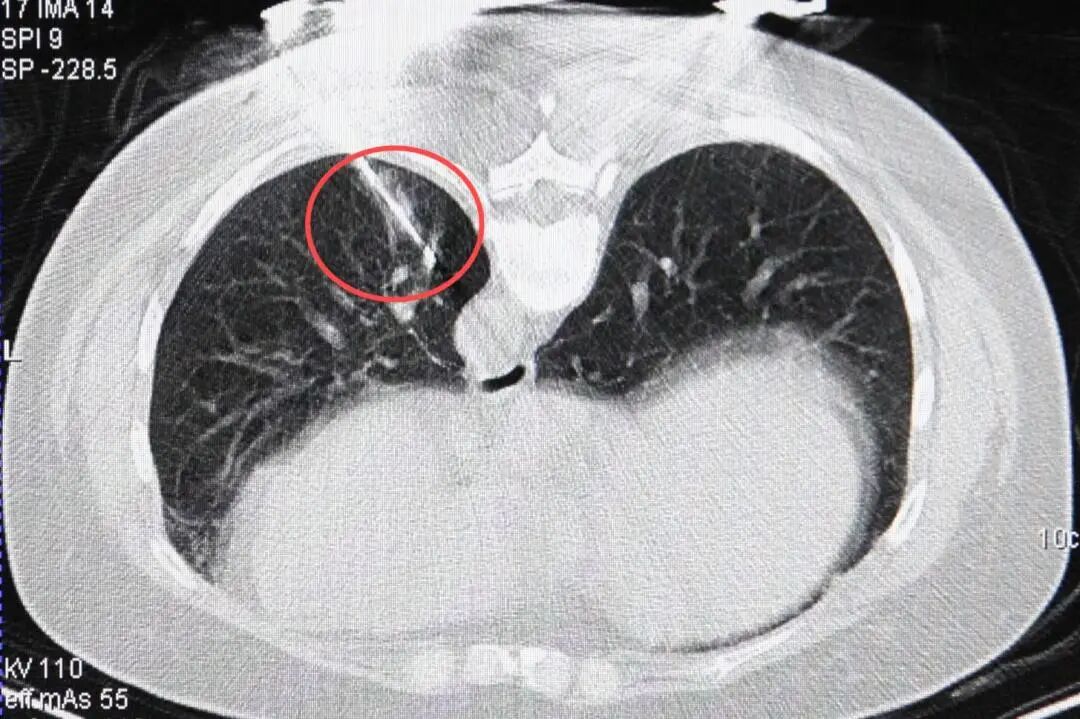

消融针精准到达病灶位置

消融后,晕征范围完全覆盖结节位置